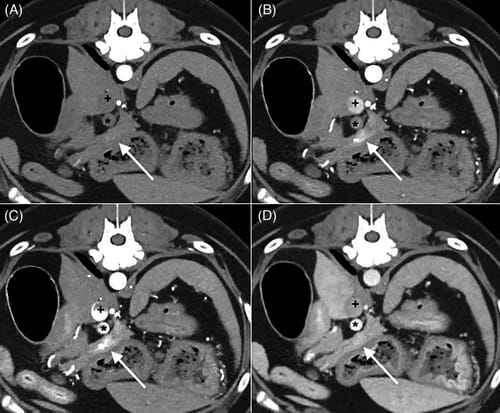

Transverse computed tomography images of a 10-year-old female neutered Labrador retriever illustrating; A, early (EAP); B, middle (MAP); C, late (LAP) arterial phases; D, venous phase. Progressive opacification of caudal vena cava (+) is noted. In LAP, the portal influx of contrast is observed in the portal vein (*). This is not observed in MAP. The arrow indicates progressive enhancement of the insulinoma graded as 0 in EAP, 2 in MAP, 3 in LAP, and 1 in venous phase. All images are displayed in soft tissue window (width: 400, level: 40), a slice thickness of 2.0 mm.